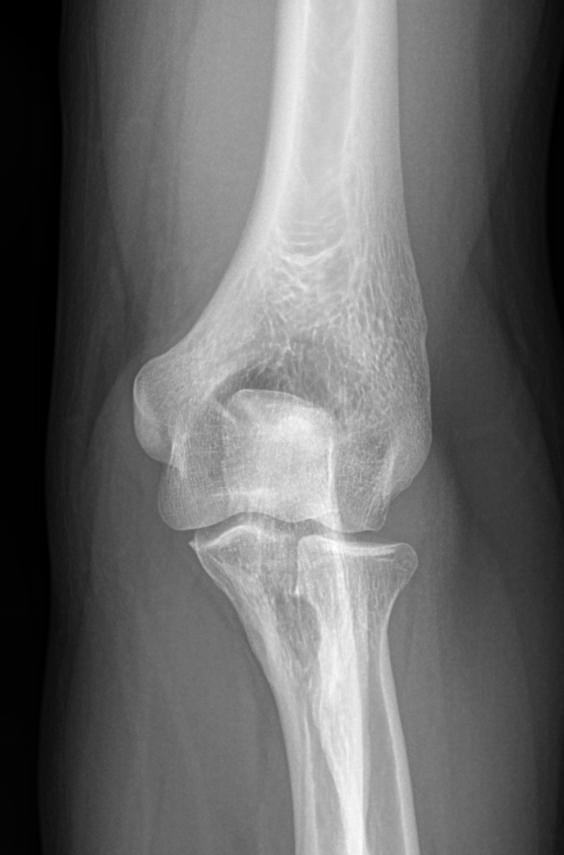

Локтевой сустав считается сложным, он состоит из 3 костей, плечевой, локтевой и лучевой, образующих, соответственно, 3 сустава. Такое строение позволяет свободно двигать рукой и поворачивать ее, обеспечивая достаточный для человека объем движений. Патологии сустава серьезно ухудшают двигательную активность и вызывают болезненные ощущения.

Что покажет рентген локтевого сустава

• Отек мягких тканей;

• Конгруэнтность и состояние суставных поверхностей, например, наличие эрозии и уплотнение суставных поверхностей, а также костные разрастания

• Состояние суставной щели ― сужение, выпот, обызвествление капсулы;

• Структура костной ткани ― типичная, деструкция или участки повышенной плотности и вздутия, остеопения, иные патологии;

• Травмы ― переломы;